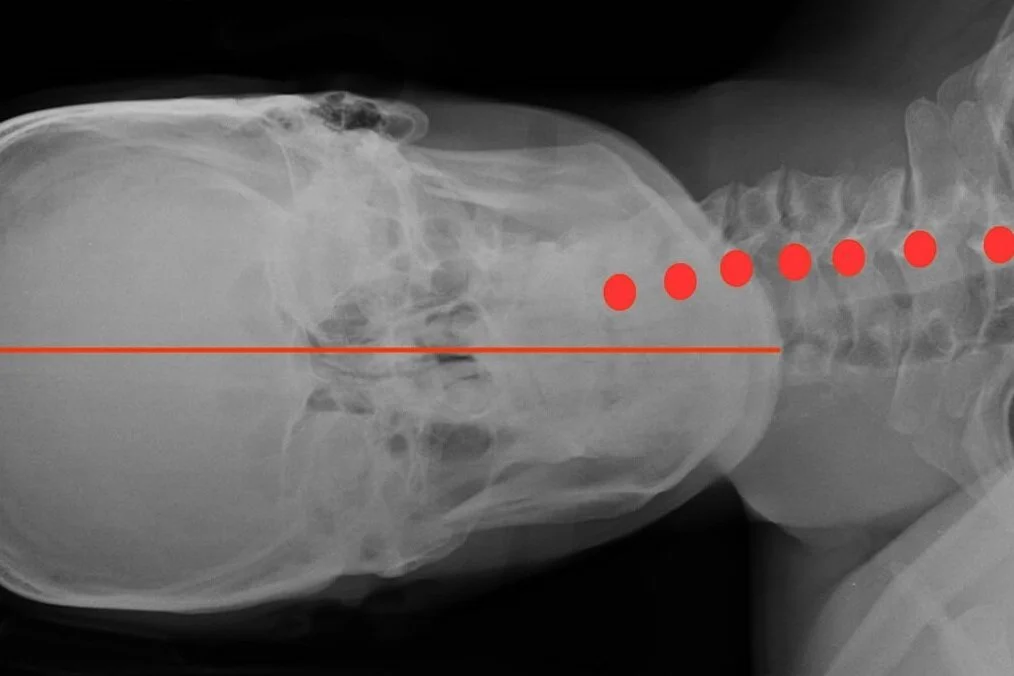

A pillow helps keep your neck and spine in comfortable alignment as you sleep. The right pillow can make a massive impact on your quality of sleep, and ultimately, your health. A pillow that is too high or too low places your neck in a tilted position. This will compress or stretch sensitive nerves, muscles and joints in the neck which can lead to restless sleep, neck pain, back pain or headaches.